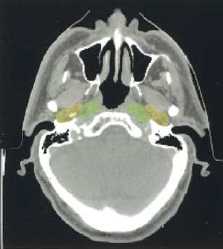

(a–l) Marked lymph nodes (LNs) with each LN group separated by color.

Light blue, submental LN (Ia);

dark blue, submandibular LN (Ib);

yellow, jugular LN (II, III, IV);

red, spinal accessory LN (V);

light green, retropharyngeal LN;

orange, parotid LN;

dark green, anterior jugular LN (VI);

pink, retroauricular/occiptal LN.